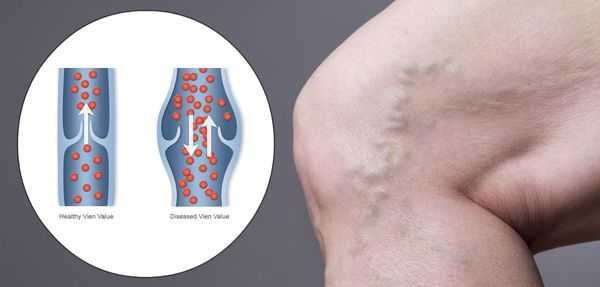

В основе развития заболевания лежит нарушение венозного оттока в нижних конечностях. При здоровой гемодинамике кровь движется от ног к сердцу за счет насосной (притягивающей) функции сердца, сокращения мышц нижних конечностей и венозных клапанов.

При этом происходит обратный сброс крови под действием гравитации вниз по венозному руслу, или венозный рефлюкс. Постепенно возникает застой крови, провоцирующий расширение подкожных вен.

Работа венозных клапанов в норме и при варикозном расширении вен